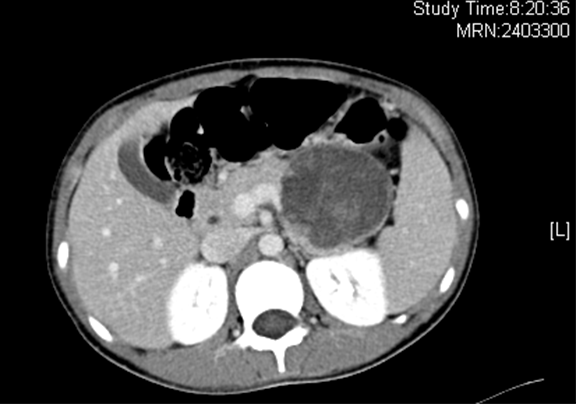

上腹部增强CT+三维:胰腺体尾部囊实性占位病变,考虑偏良性肿瘤可能性大,建议MR 进一步检查

术前CT检查:

动脉期

静脉期

平衡期